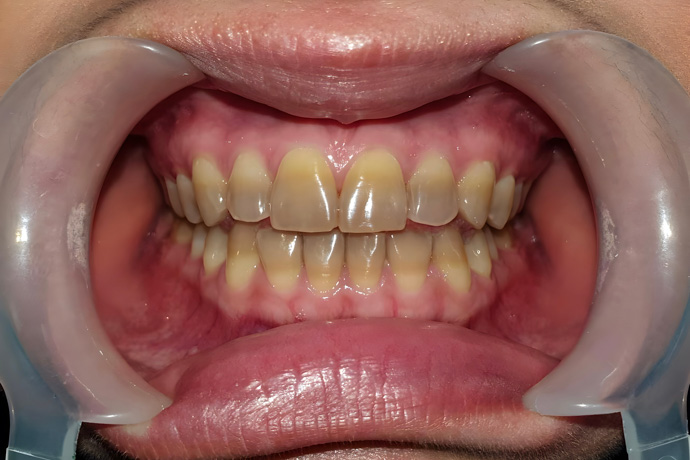

Fumar o masticar productos de tabaco hace que el esmalte dental se deteriore. Healthline señala que esto sucede por la presencia de componentes como la nicotina y el alquitrán, que hacen que los dientes se oscurezcan e incluso empiecen a verse marrones.

Las manchas causadas por el tabaco se forman cuando sustancias como el alquitrán y la nicotina entran en contacto con los dientes, ya sea a través del humo o de productos masticables de tabaco. Estos químicos se depositan sobre el esmalte de los dientes, y forman una capa que los mancha.

Impacto estético de los dientes manchados

La apariencia de los dientes es la primera en sufrir por el consumo de tabaco, ya que, como mencionamos antes, los químicos del tabaco afectan el esmalte de los dientes. Los dientes amarillos o marrones de los fumadores afectan la percepción de higiene personal, y pueden ser causa de problemas de confianza y autoestima.